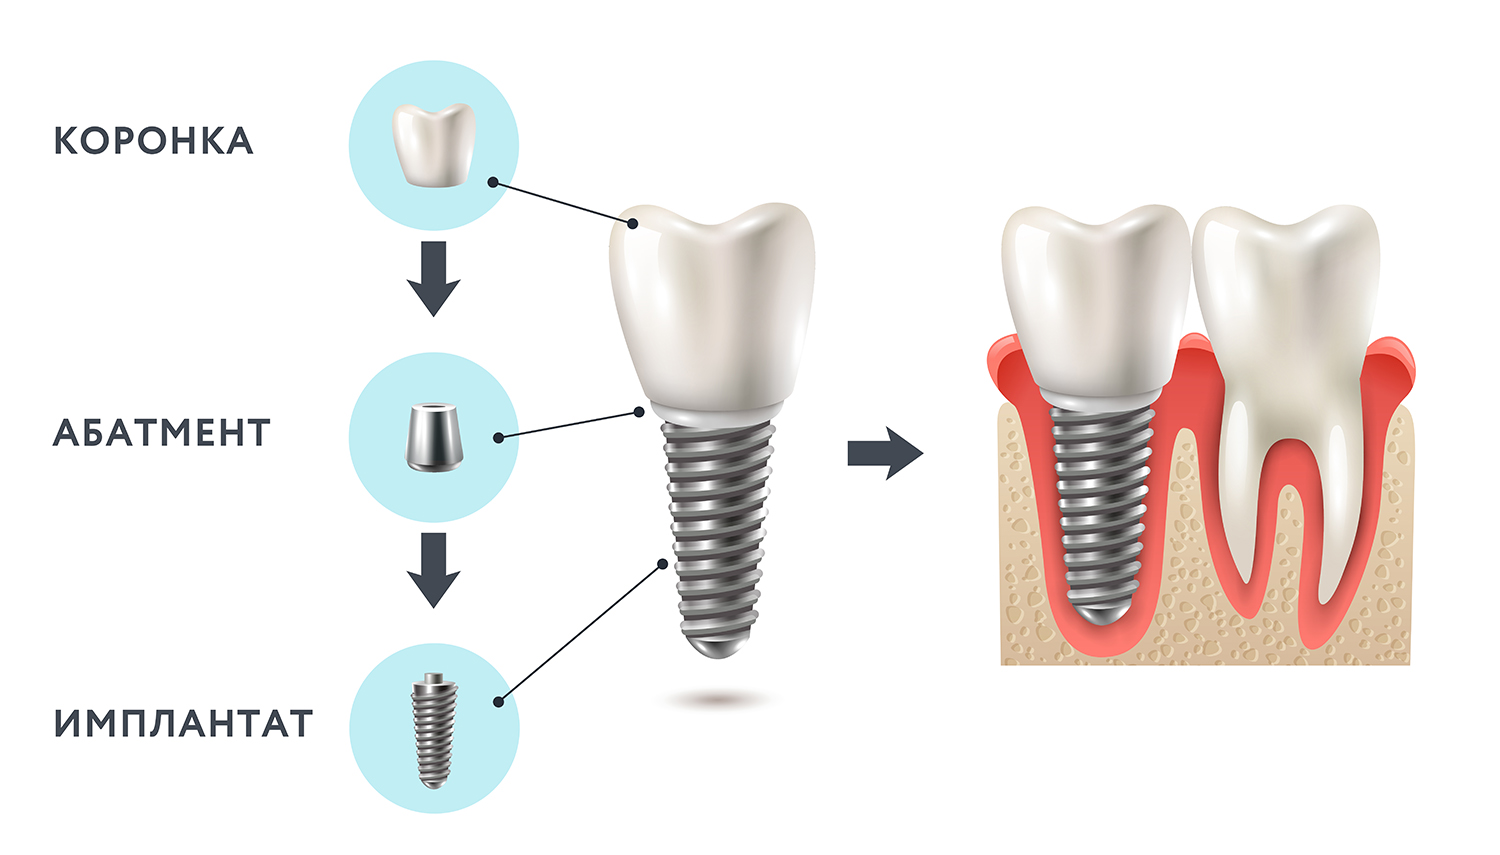

Современная стоматология: Железные зубные импланты